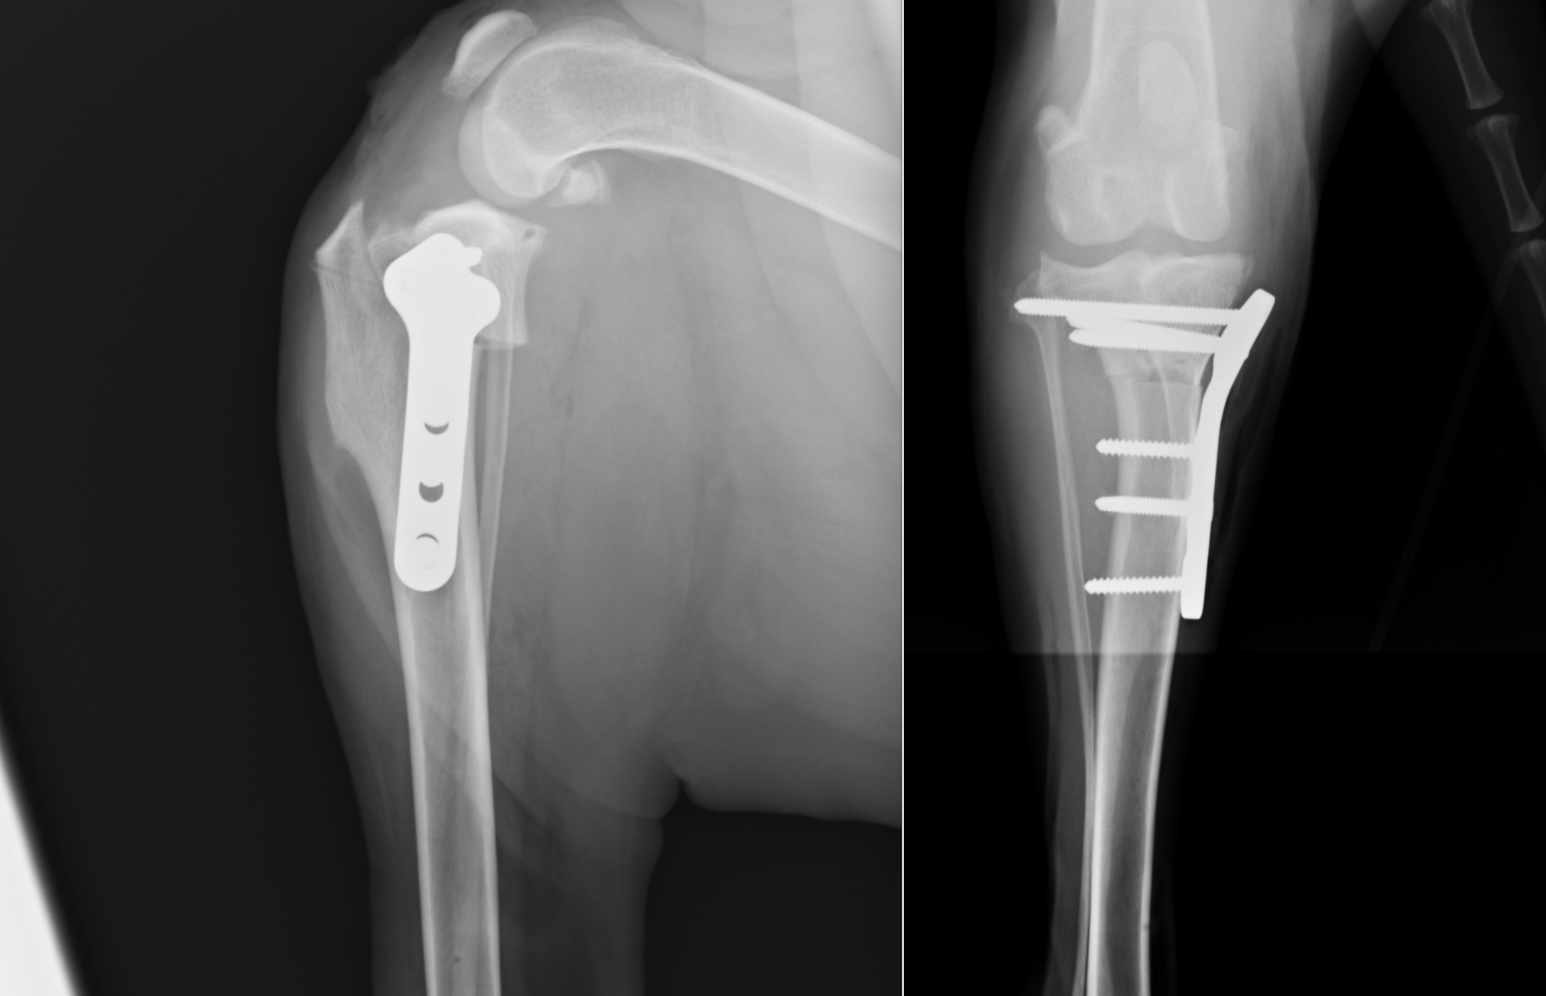

術後のレントゲン画像です。先程までずれていた矢印が合っているのがわかります。

またTPAと呼ばれる角度も小さくなっているのが確認できます(6°)。6°前後が理想的と言われています。

4kgのチワワです。術後TPA-4°となっており、経過は順調でした。2mmのプレートでギリギリのサイズです。

2kgのヨークシャテリアです。現存するTPLOプレートの中では最も小さい1.5mmのプレートを用いています。また、骨を切るブレードも特殊なものを用いており、8mmというサイズを使用して切っています。術後TPA1°となっており、術後は順調で、術後3日後には4本足で歩行可能となりました。2週間後には走ることまで可能となっていました。

40kgのバーニーズマウンテンドッグです。11歳と高齢でしたが、7日目には跛行があったものの、4本足で帰宅することが可能でした。

7kgのトイプードルです。カーブプレートという少し特殊なプレートを用いています。術後4日目には4本足で歩行が可能となりました。